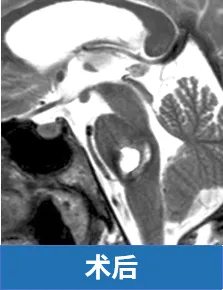

INC巴特朗菲教授(巴教授)在精细清除血肿及血管畸形的同时,特别注意保护脑桥后部实质及外展神经、面神经的完整性。

术后一年,明显可以看到劳拉的面神经和外展神经功能已基本恢复,面瘫不再,喜笑颜开。

上述真实案例及图片来自于INC巴特朗菲教授课程演讲。